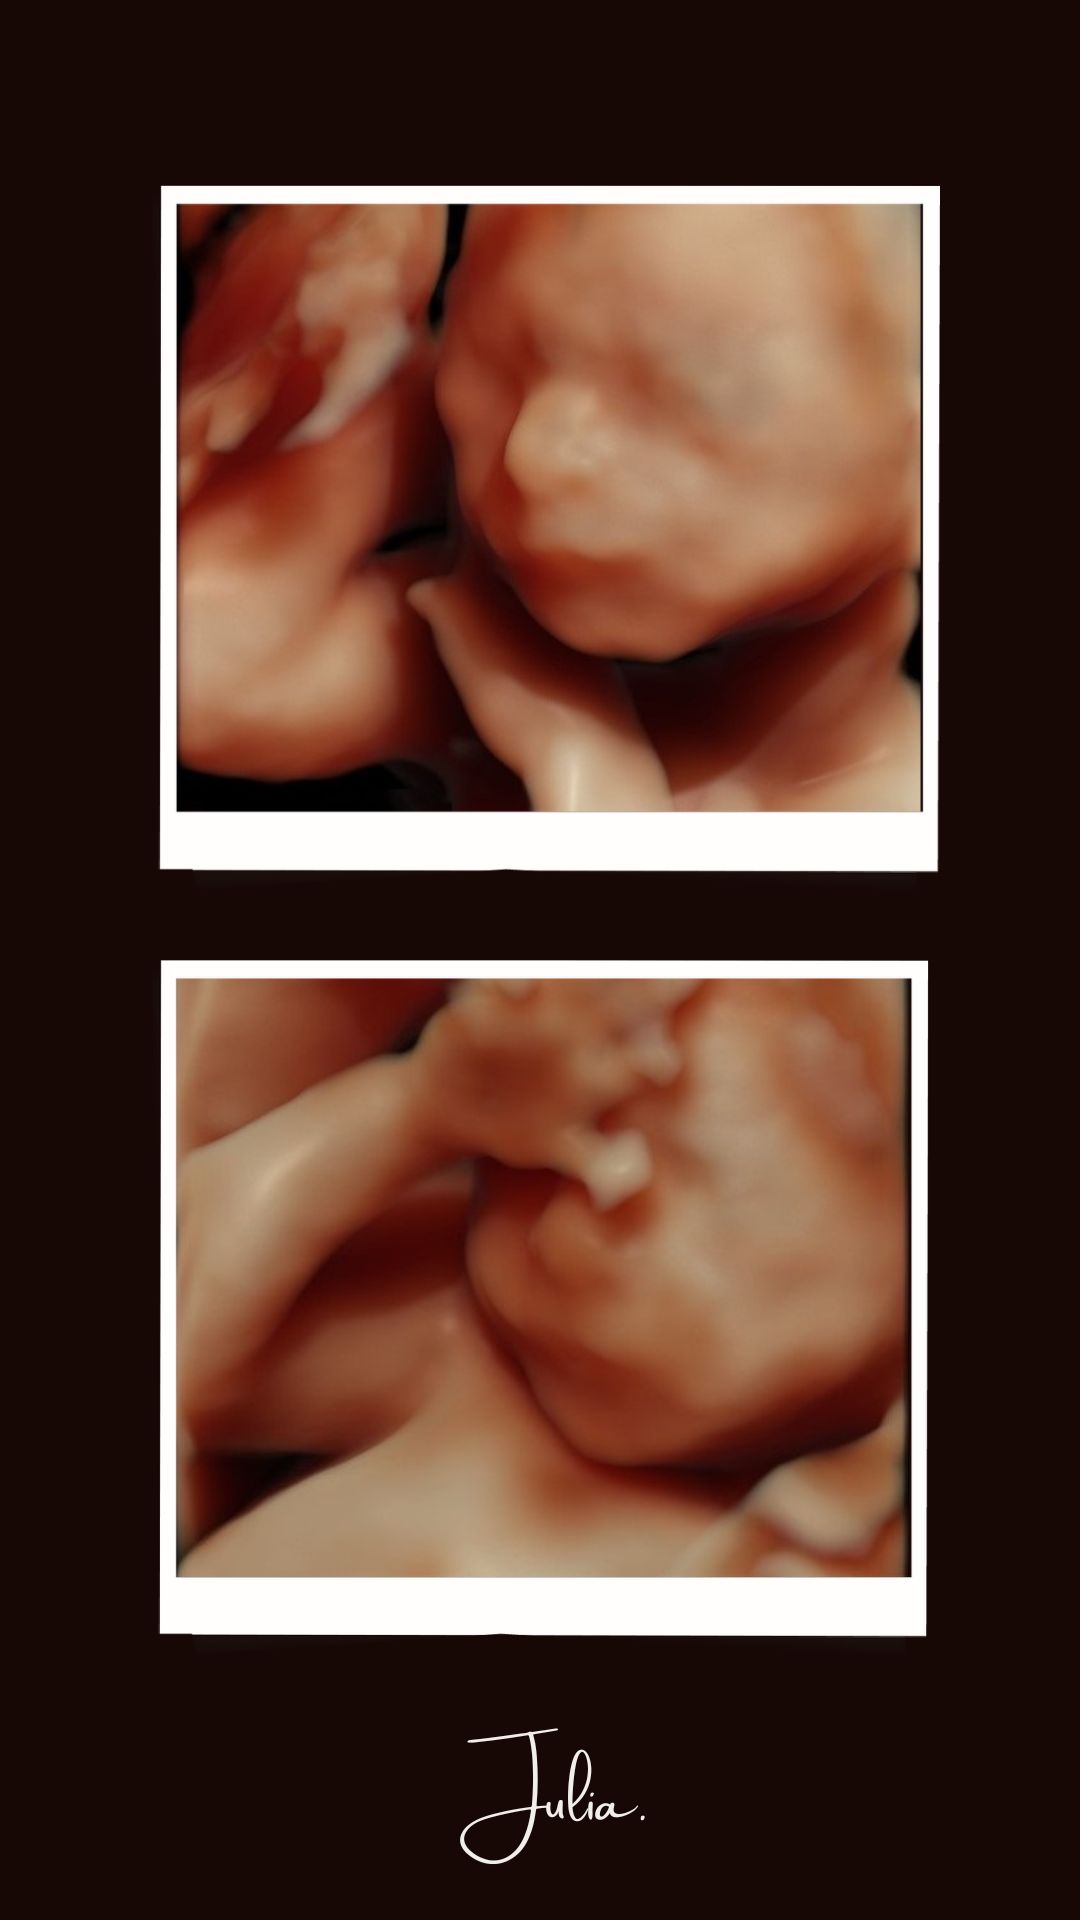

Object Imagem 3.jpg

Object 1.jpg